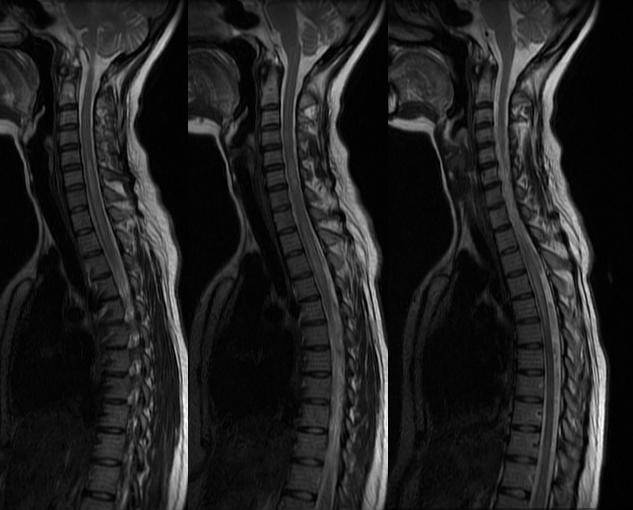

Врачи подчеркивают, что выявление грыжи в грудном отделе позвоночника требует комплексного подхода. Первым шагом является тщательный сбор анамнеза, в ходе которого специалист уточняет симптомы, такие как боль в спине, онемение или слабость в руках. Далее, для более точной диагностики, назначаются рентгенографические исследования и магнитно-резонансная томография. Эти методы позволяют визуализировать состояние межпозвоночных дисков и выявить наличие грыжи. Важно также обратить внимание на неврологические тесты, которые помогают оценить функциональное состояние нервных корешков. Врачи настоятельно рекомендуют не игнорировать первые признаки заболевания и обращаться за медицинской помощью, чтобы избежать серьезных осложнений.

Медики рекомендуют проводить диагностику с помощью МРТ или КТ, так как эти методы позволяют точно определить наличие грыжи и её размеры. Люди также делятся опытом о том, как важна ранняя диагностика: чем раньше выявлена проблема, тем легче её решить. В целом, осведомленность о симптомах и своевременное обращение к специалистам играют ключевую роль в успешном лечении.

- МРТ: метод полностью подходит для идентификации грыжи, определения ее локализации и стадии;

Одним из основных методов диагностики является магнитно-резонансная томография (МРТ). Этот метод позволяет получить детализированные изображения мягких тканей, включая межпозвонковые диски и нервные структуры, что помогает точно определить локализацию и степень грыжи.

Магнитно-резонансная томография (МРТ) — лучший инструмент для наблюдения и диагностики проблем с межпозвоночными дисками. Могут использоваться и другие методы визуализации, такие как рентген или компьютерная томография (КТ), но они не так точны, как МРТ в диагностике грыжи грудного диска.